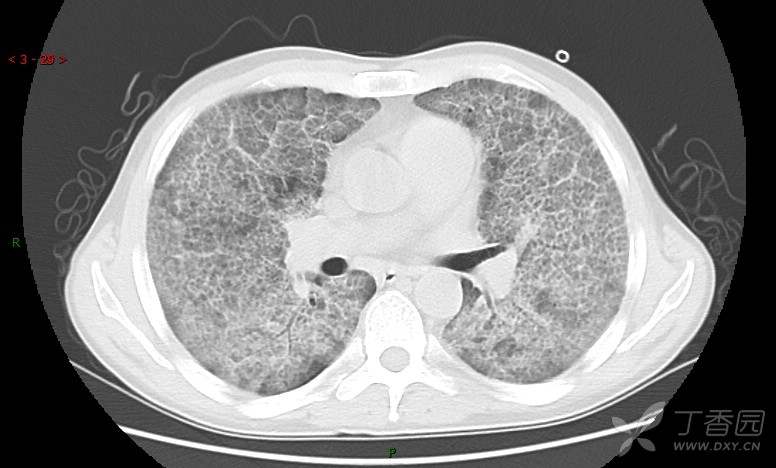

地图+铺路石征=PAP?那升高的CEA怎么说(病例3连发,附其他2例链接)

患者男,42岁,咳嗽半年余,加重伴憋喘2月余。

血清肿瘤相关抗原116.22U/ml↑(0--95);

癌胚抗原 61.96 ng/mL ↑ 0--5

神经特异性烯醇化酶 33.12 ng/ml ↑ 0--16.3

细胞角蛋白19片段测定 40.23 ng/ml ↑ ≤3.3

肺内弥漫性网状结节影,PET-CT却无阳性病灶,这是?(附其他2例链接)